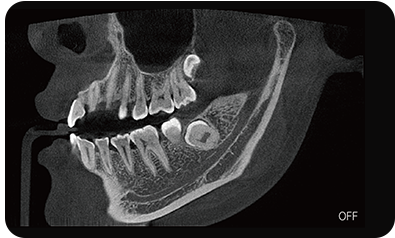

临床样片